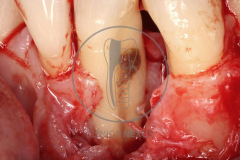

Tratamiento de defectos periodontales infraóseos en sector antero-inferior empleando gel de amelogeninas (Emdogain®) en combinación con un aloinjerto óseo (Biobank®). Paciente de 64 años, sin problemas médicos de relevancia, que presenta una periodontitis leve generalizada, pero asociada a presencia de defectos óseos verticales profundos a nivel de los espacios interdentales entre los caninos y los incisivos laterales inferiores. Tras la pertinente fase higiénica, se llevó a cabo una cirugía periodontal regenerativa, en la que, tras eliminar el cálculo subgingival (factor causal), se empleó una combinación de amelogeninas con un aloinjerto, para promover la regeneración tisular del periodonto perdido. Las imágenes clínicas y radiológicas, al año de seguimiento, reflejan un resultado terapéutico óptimo, con regeneración completa del tejido periodontal y mejora del pronóstico de los dientes involucrados.